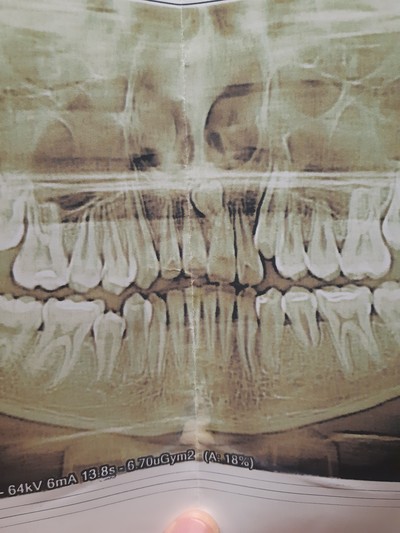

Так вот в один из таких погожих деньков в клинику обратился пациент с жалобой на дискомфорт на нижней челюсти. Ну, видать, зуб мудрости дал о себе знать, думаю я, дело то житейское. Направил на компьютерную томографию, а сам пошел попить чайку с мыслями о том, что без труда, не заморачиваясь, удалю зуб и дело с концом. Размешиваю, значит, сахарок, делаю глоток… Хорошо, думаю, сейчас бы выходной, да на фазенде, а не вот это вот все… Через несколько минут приходит ассистентка с растерянным выражением лица. Ну что, вопрошаю я, пойдем быстренько зуб удалим? Поставил стакан с чаем на стол, уверенный, что успею вернуться до того, как он остынет. Итак, мы с ассистенткой и ее недвусмысленной улыбой пошли в рентгеновский кабинет. И вот, что я увидел на компьютерной томографии:

«Сссука», – мимолетно проскользнуло у меня в голове. Так вот почему лицо ассистентки было таким. В голове крутились мысли: «ведь эта штука росла годами, а раз пациент не обращался к стоматологу, значит, не беспокоила». Вот вам, думаю я, и «не пойду к врачу, пока не заболит».

На нижней челюсти слева у пациента была внушительных размеров фолликулярная киста, которая занимала половину ветви челюсти.